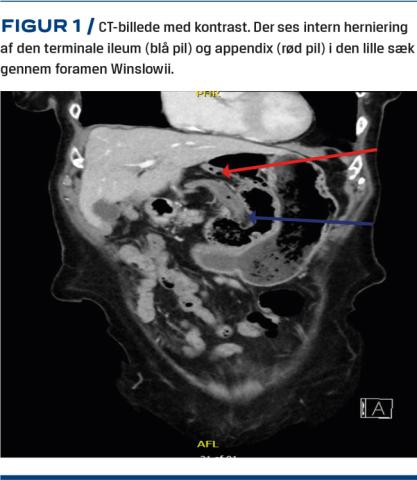

Første mistanke om galdestensanfald blev afkræftet ved en UL-skanning af abdomen, som var upåfaldende. Pga. tiltagende og morfikakrævende smerter blev der bestilt en CT af abdomen, hvorved man fandt intern herniering af caecum, den terminale ileum og den orale colon ascendens i den lille sæk gennem foramen Winslowii (Figur 1). Der var dog intet tegn på ileus eller tarmiskæmi.